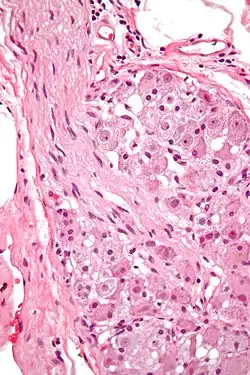

Ganglion cells within a ganglion. H&E stain.

In neurophysiology, a ganglion cell is a cell found in a ganglion (a cluster of neurons in the peripheral nervous system). Depending on their location and function, ganglion cells can be categorized into several major groups: